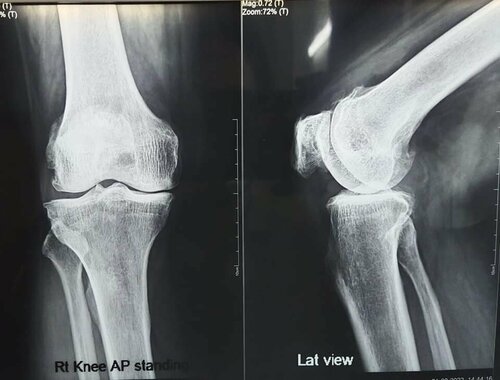

60-year male undergoes Bilateral Total Knee Replacement | Dr. Jagdish Dhake

60-year male, had bilateral osteoarthritis knee, K/c/o obstructive sleep apnea. He was operated successfully by Dr. Jagdish Dhake - Orthopedic Surgeon...